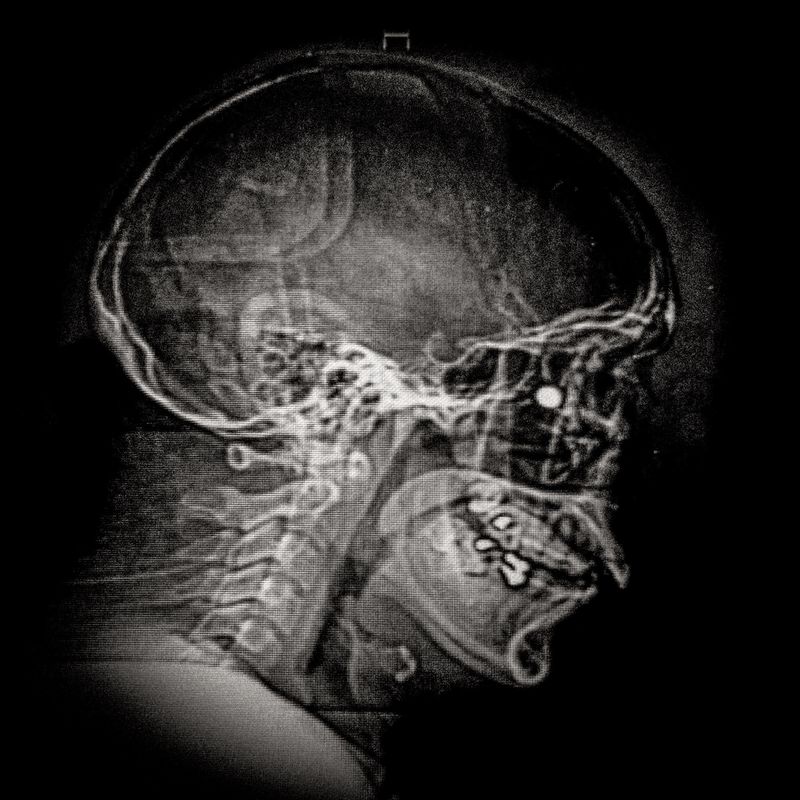

X-ray showing the pellet embedded in the skull of Ybar Soto (29) Ybar was hit by a pellet that lodged in his right eye on October 24, 2019 in Plaza Italia. Santiago. His diagnosis was ocular burst. Santiago, Chile. December 28, 2019